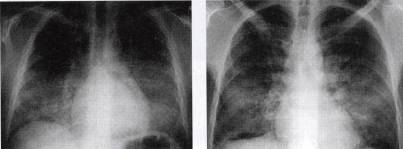

以双侧肺门为中心对称分布的大片状阴影,肺门区密度较高边缘模糊,而肺野外带正常,形如蝶翼,称为蝶翼征。见图1。

图1肺泡蛋白沉积症的胸部X线表现